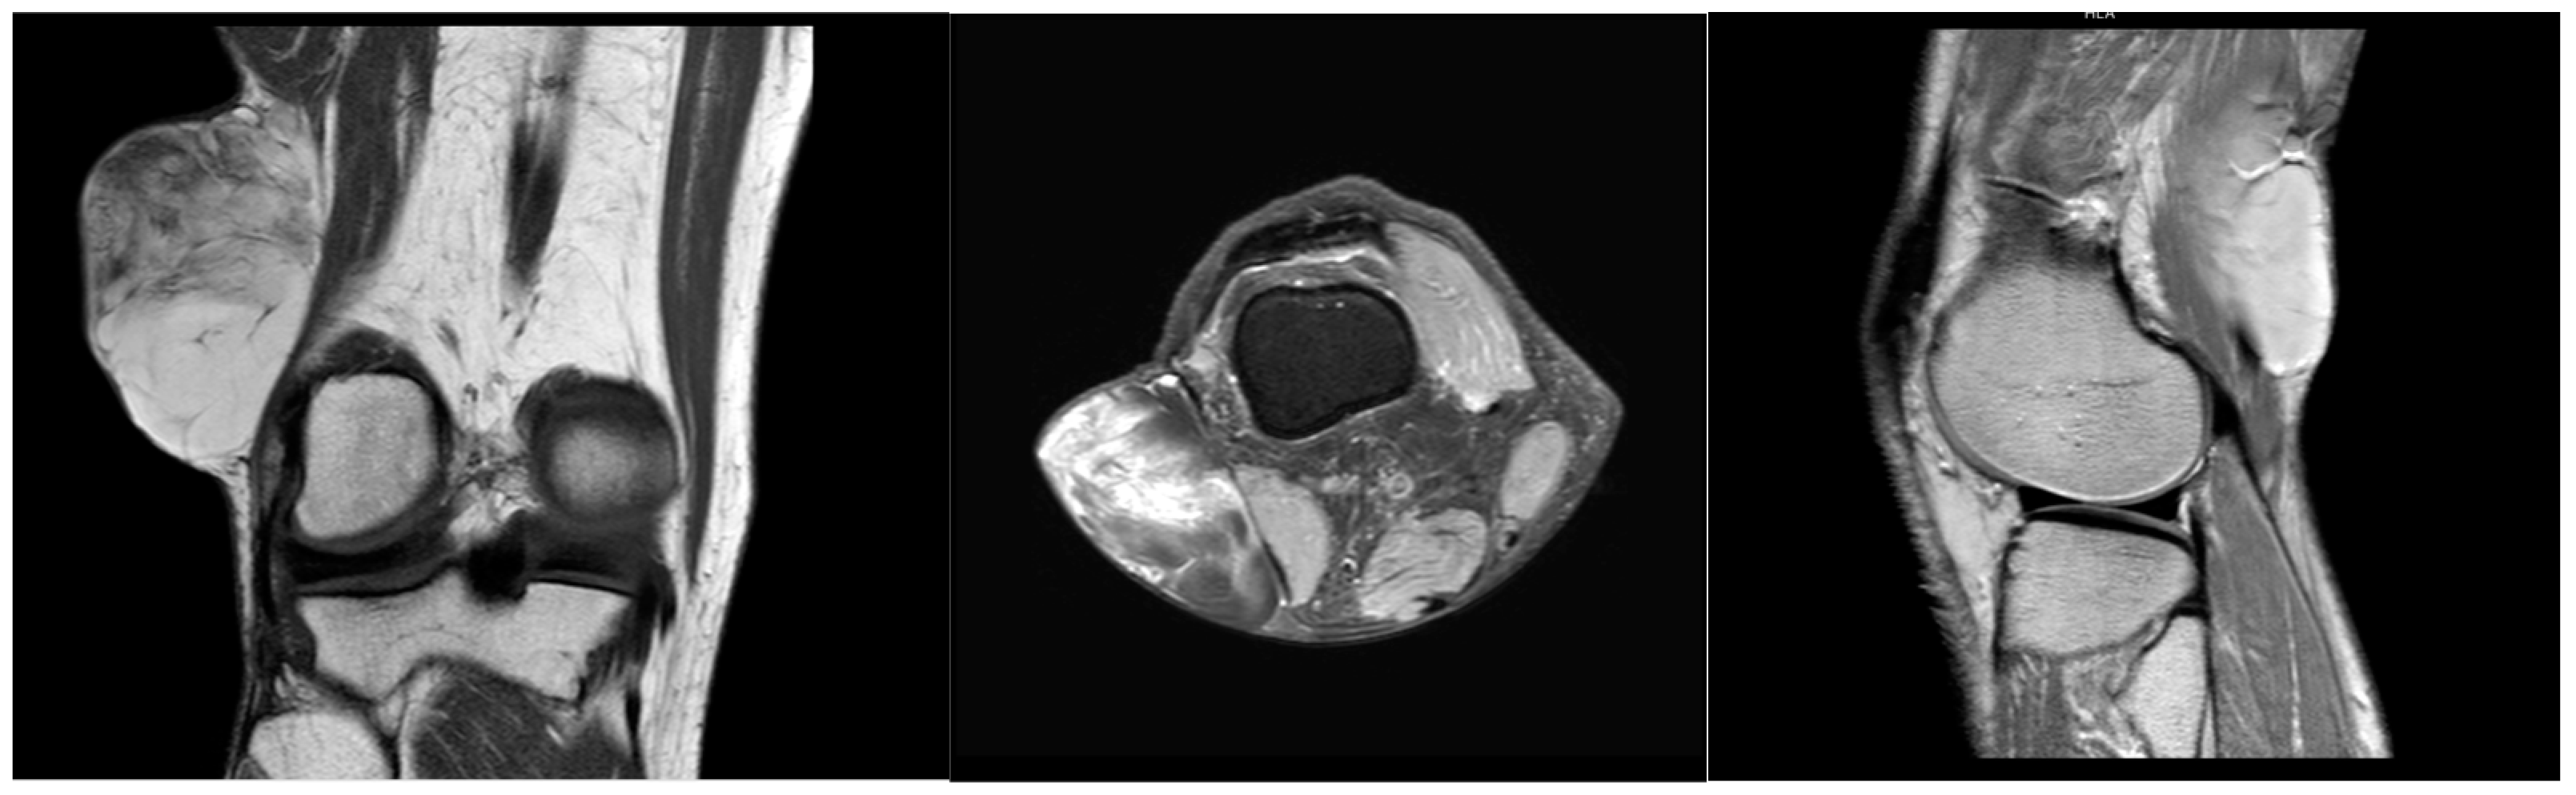

A 64-year-old male with a history of hypertension and heavy alcohol consumption was referred to us by his primary provider with a longstanding mass in the right popliteal region. The patient reported an absence of pain and no restriction in their range of motion, although he observed a gradual increase in mass size over six years. The initial examination six years ago revealed a painless, small soft tissue mass in the popliteal fossa. Further assessment at that time employing ultrasound confirmed a mobile soft tissue mass measuring 4.2 cm × 2.4 cm × 3.6 cm, subsequently confirmed via core needle biopsy as a lipoma. Close patient monitoring over the ensuing six years revealed a nearly twofold increase in mass dimensions. Therefore, a contrasted MRI was performed, which exhibited homogeneous, low signal intensity on a T1-weighted pulse sequence and heterogenous, high signal intensity on T2-weighted pulse sequence for the mass within the popliteal fossa, measuring 8.0 cm × 7.0 cm × 5.0 cm (Figure 1). The mass was subcutaneous and located proximate to the rectus femoris and distal aspect of the vastus lateralis muscle. Areas of septations were observed within the mass, raising concerns regarding the possibility of liposarcoma.

Figure 1.

MRI coronal, transverse, and sagittal view of right popliteal fossa mass.